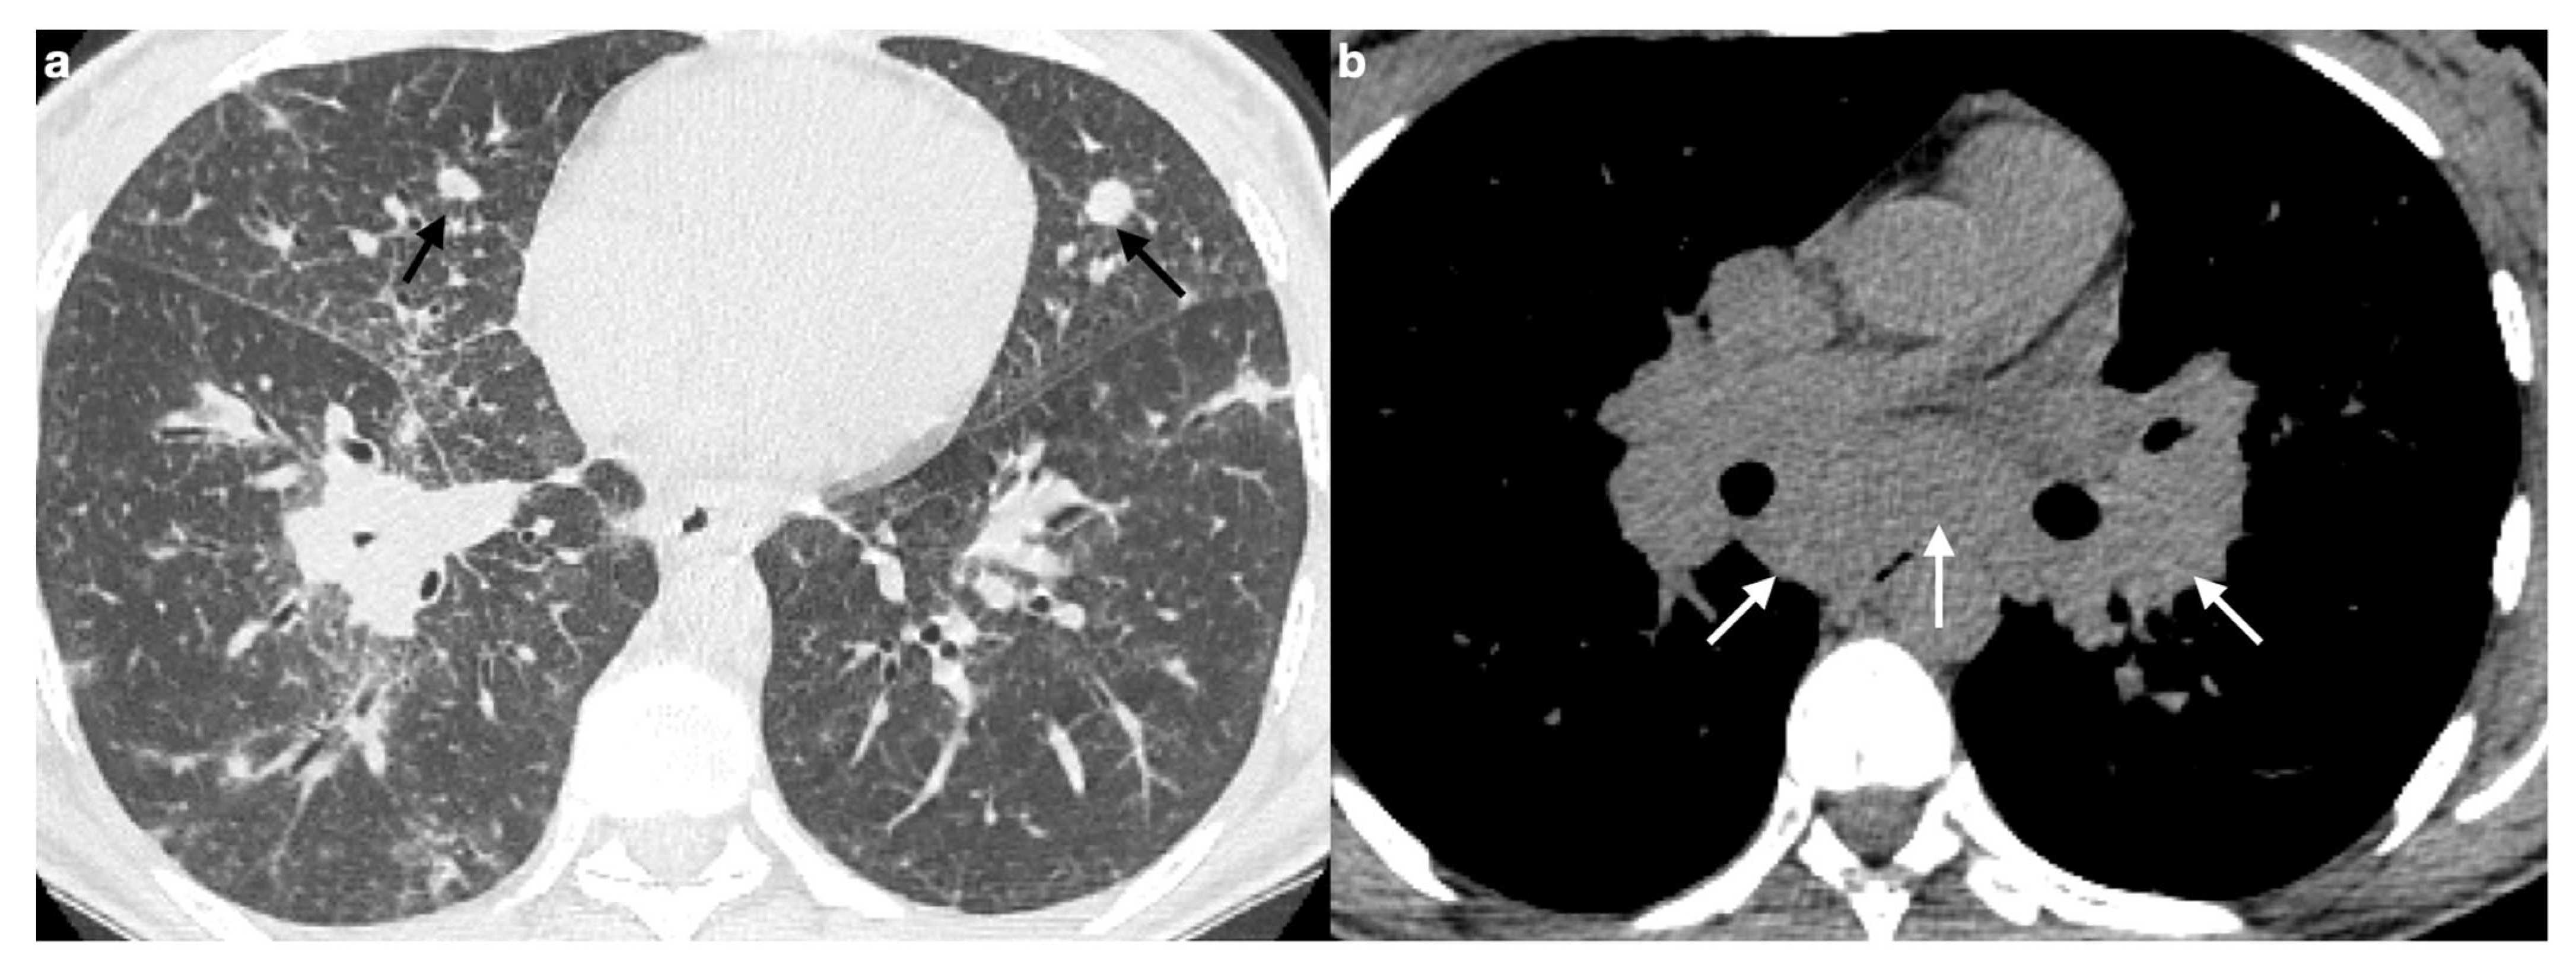

7. Pulmonary Hypertension

- Polychronopoulos, V.S.; Prakash, U.B.S. Airway Involvement in Sarcoidosis. Chest 2009, 136, 1371–1380. [Google Scholar] [CrossRef]

- Lenique, F.; Brauner, M.W.; Grenier, P.; Battesti, J.P.; Loiseau, A.; Valeyre, D. CT assessment of bronchi in sarcoidosis: Endoscopic and pathologic correlations. Radiology 1995, 194, 419–423. [Google Scholar] [CrossRef]

- Huitema, M.P.; Spee, M.; Vorselaars, V.M.M.; Boerman, S.; Snijder, R.J.; Van Es, H.W.; Reesink, H.J.; Grutters, J.C.; Post, M.C. Pulmonary artery diameter to predict pulmonary hypertension in pulmonary sarcoidosis. Eur. Respir. J. 2016, 47, 673–676. [Google Scholar] [CrossRef]